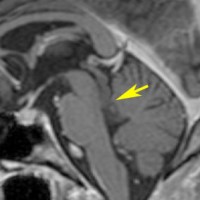

17歳で滑車神経麻痺で発症した例

中脳左下丘から上髄帆が腫大しています。滑車神経の出口にあたる部分が侵されていて症状と一致する所見です。右側のガドリニウム増強T1でも増強される部分はありません。確かにtectal gliomaの性質を有していて,3年間ほとんど動きませんでした。piaを押して突出するような腫瘤形成があり,diffuse astrocytomaともまた違う画像所見と言えます。滲み込む infiltrateというより,塊 solid massを作るという形質があるのがtectal gliomaでしょう。